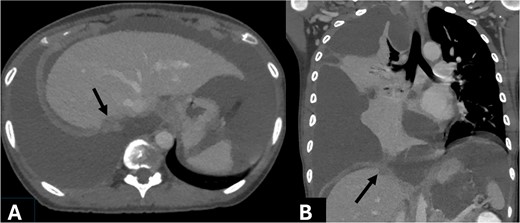

A 33-year-old Asian female presented with progressive dyspnea for 1 month. Physical examination revealed decreased breath sounds at right lung with dullness on percussion and abdominal distension. A chest X-ray showed a large right-sided haziness (Fig. 1). Blood test revealed hemoglobin 11.9 g/dl, WBC 13 200 cells/mm3, protein 8.3 g/dl, albumin 3.5 g/dl, total bilirubin 0.5 mg/dl, direct bilirubin 0.13 mg/dl, and alkaline phosphatase 67 U/l. Computed tomography (CT) scan demonstrated a large amount of ascites and right pleural effusion, 1.5-cm peritoneal nodule at the right subdiaphragmatic surface (Fig. 2), multiple ovarian cysts, and 2.6-cm hypodense lesion at posterior wall of cervix abutting upper rectum.

Axial (A) and coronal (B) contrast enhanced CT obtained during portovenous phase showed right subdiaphragmatic enhancing nodule attaching right hepatic capsule, measuring 15 mm (arrow). Massive complicated right pleural effusion caused compressive atelectasis at lower part of right lung. Large amount of ascites was noted.